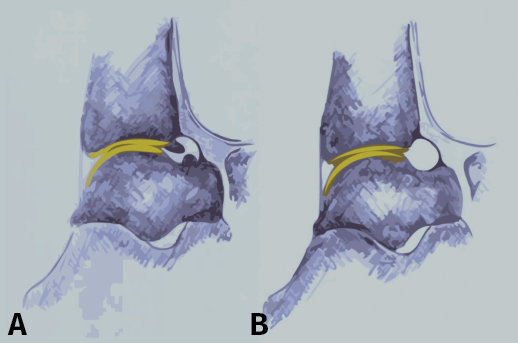

El dolor relacionado con el pinzamiento del tobillo anterior de tipo óseo está probablemente causado por la inflamación de los tejidos blandos (ligamentos, tendones), que se hallan comprimidos por los osteofitos del astrágalo y/o la tibia durante las fuerzas de dorsiflexión (Figura 1)(9,10,11). Existen varias teorías sobre la posible etiología de la formación de osteofitos que producen el síndrome doloroso de pinzamiento del tobillo anterior(12), principalmente basadas en factores mecánicos, inestabilidad crónica del tobillo, microtraumatismo recurrente y/o tracción(1,3,8,13).

Figura 1. Vista de pinzamiento óseo anterior por osteofitos. El tejido sinovial inflamado se comprime entre los osteofitos del astrágalo y la tibia durante la flexión dorsal forzada, lo que probablemente causa el dolor relacionado con el pinzamiento óseo en estos procesos.

Figura 3. Visión lateral de un tobillo que muestra la zona de cartílago anterior de la tibia y la inserción de la cápsula. A: los osteofitos están a nivel distal de la tibia y en talus; B: anatomía tras resecar los osteofitos.